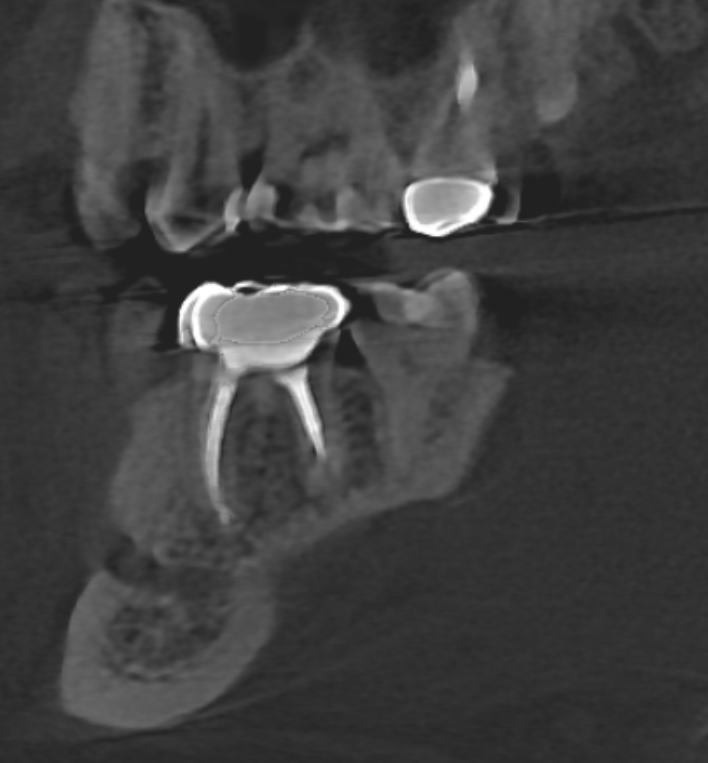

Зуб шестёрка снизу слева с коронкой. Правильно ли я понимаю, что семёрка с кариесом? И как оцениваете качество посадки коронки? Есть ли вероятность, что из-за неправильной установки коронки развился кариес на семёрке? Коронка стоит всего 2.5 года. Семёрка тогда же лечилась от кариеса.

Чтобы оценивать качество лечения, надо иметь качественное обследование!